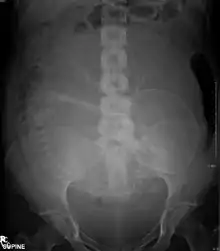

Abdominal radiograph of a pregnant woman

Projectional radiographs are useful in the detection of pathology of the skeletal system as well as for detecting some disease processes in soft tissue. Some notable examples are the very common chest X-ray, which can be used to identify lung diseases such as pneumonia, lung cancer, or pulmonary edema, and the abdominal X-ray, which can detect bowel (or intestinal) obstruction, free air (from visceral perforations), and free fluid (in ascites). X-rays may also be used to detect pathology such as gallstones (which are rarely radiopaque) or kidney stones which are often (but not always) visible. Traditional plain X-rays are less useful in the imaging of soft tissues such as the brain or muscle. One area where projectional radiographs are used extensively is in evaluating how an orthopedic implant, such as a knee, hip or shoulder replacement, is situated in the body with respect to the surrounding bone. This can be assessed in two dimensions from plain radiographs, or it can be assessed in three dimensions if a technique called '2D to 3D registration' is used. This technique purportedly negates projection errors associated with evaluating implant position from plain radiographs.[101]

The risk of radiation is greater to a fetus, so in pregnant patients, the benefits of the investigation (X-ray) should be balanced with the potential hazards to the fetus.[119][120] If there is 1 scan in 9 months, it can be harmful to the fetus.[121] Therefore, women who are pregnant get ultrasounds as their diagnostic imaging because this does not use radiation.[121] If there is too much radiation exposure there could be harmful effects on the fetus or the reproductive organs of the mother.[121] In the US, there are an estimated 62 million CT scans performed annually, including more than 4 million on children.[109] Avoiding unnecessary X-rays (especially CT scans) reduces radiation dose and any associated cancer risk.[122]